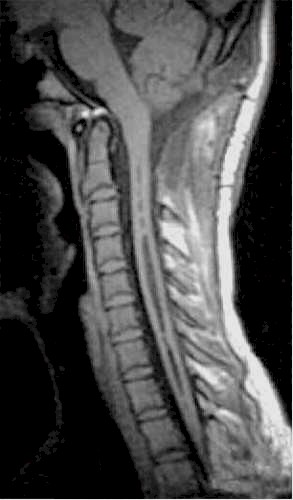

| Siringomielia

cervico-dorsale RM. |

Esito

postchirurgico. |

Due

anni dopo. |